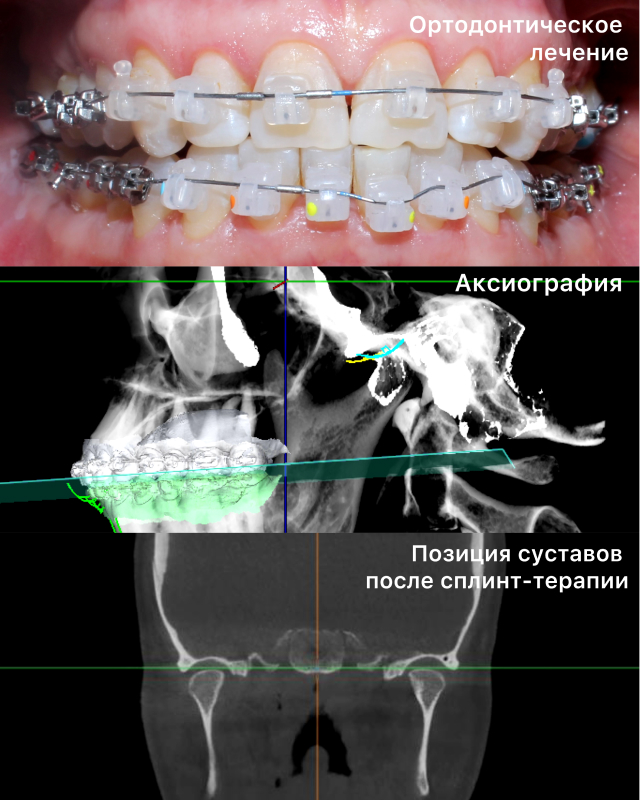

После диагностики мы приступили к реабилитации прикуса. Заменили все несостоятельные ортопедические конструкции и начали исправление прикуса. Дойдя до финального этапа ортодонтического лечения, провели аксиографию, нашли ЦС(центральное соотношение) и с помощью сплинт-терапии устранили щелчок в суставе. Получив новое положение челюсти, закрепили результат временным протезированием с контрольными снимками КТ и МРТ.